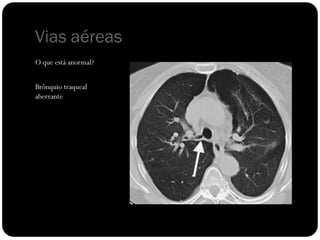

O que está anormal?

Vias aéreas

Brônquio traqueal

aberrante